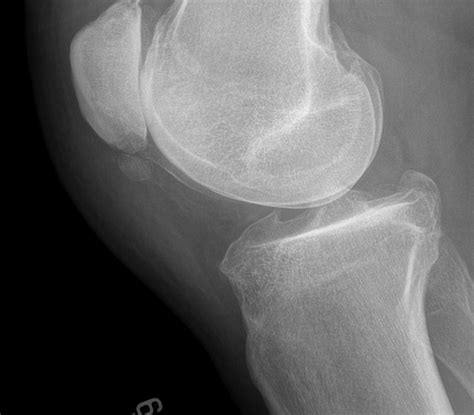

• Imaging tests: X-rays, ultrasound, or MRI scans can help visualize the calcium deposits and assess the extent of the damage.